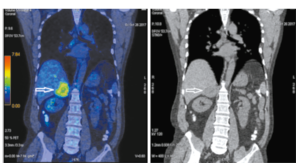

Через 32 мес пациент жив без признаков прогрессирования заболевания. По данным ПЭТ/КТ от 27.05.2020 первичной опухоли почек не выявлено (рис. 8).

Рис. 8а-8б. На корональных ПЭТ/КТ- (а) и КТ-проекциях (б) очагов повышенного метаболизма и патологических образований не выявлено. На аксиальных ПЭТ/КТ- (в) и КТ-проекциях (г) литический очаг в ножке L3 прежних размеров без фиксации радиофармпрепарата.

Fig. 8a-8b. PET/CT (a) and CT images in coronal projection did not show increased metabolism or pathological formations (b). PET/CT (c) and CT images in axial projection (d) showed lytic lesion in L3 articular process of the same size without accumulation of the radiopharmaceutical.

Рис. 8в-8г. На корональных ПЭТ/КТ- (а) и КТ-проекциях (б) очагов повышенного метаболизма и патологических образований не выявлено. На аксиальных ПЭТ/КТ- (в) и КТ-проекциях (г) литический очаг в ножке L3 прежних размеров без фиксации радиофармпрепарата.

Fig. 8c-8d. PET/CT (a) and CT images in coronal projection did not show increased metabolism or pathological formations (b). PET/CT (c) and CT images in axial projection (d) showed lytic lesion in L3 articular process of the same size without accumulation of the radiopharmaceutical.